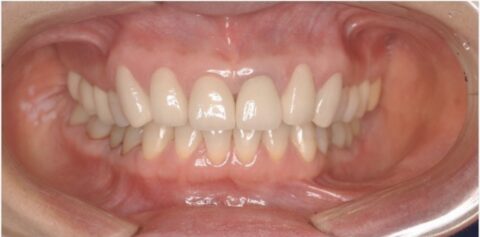

また、白い綺麗な歯並びを獲得したことにより綺麗な口元を獲得できています。

横向きや正面から見た印象もこの様に違いますね。